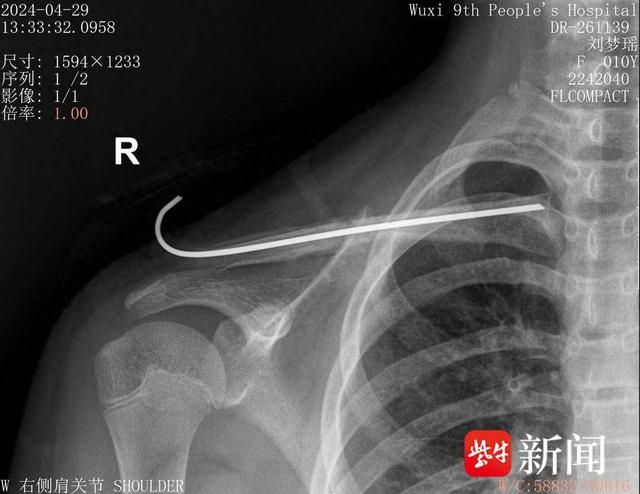

术后一个月骨愈合摄片

据悉,常规手术需行切开复位钢板内固定,但大切口一方面易影响骨折断端血供,另一方面易造成切口疤痕从而影响美观。近年来,随着微创治疗理念的推广,无锡九院小儿骨科已常规开展小切口辅助复位行克氏针、髓内钉固定手术。但孩子不同于成人,大多锁骨髓腔细小、闭合复位困难,因此这一微创手术操作对精准度提出了更高要求。印飞医生和团队通过“天玑”骨科机器人详细采集患儿小紫的数据,精准规划手术路径,锚定进针位置和方向后,“按图索骥”完成锁骨干骨折的闭合复位克氏针髓内固定手术。术后,小紫的伤处仅留下数枚针眼孔。

小儿骨科副主任林伟枫介绍,骨折患儿是临床中的一类特殊群体,手术治疗的目的是减轻疼痛、降低后遗症并尽早帮助他们重返校园。在“天玑”骨科机器人的辅助下,可真正实现“零切开”锁骨骨折治疗,既避免了二次手术风险,又不会留有明显手术疤痕。